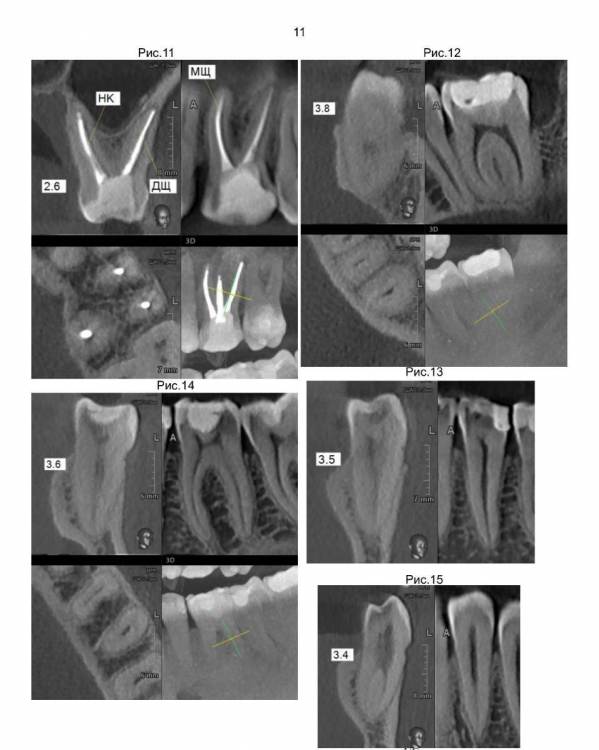

По второму плану лечения зубы 2.6 и 4.6 стачиваются, устанавливаются корневые вкладки и ставятся коронки.

И по третьему плану лечения зубы 1.8 и 3.8 просто удаляются.